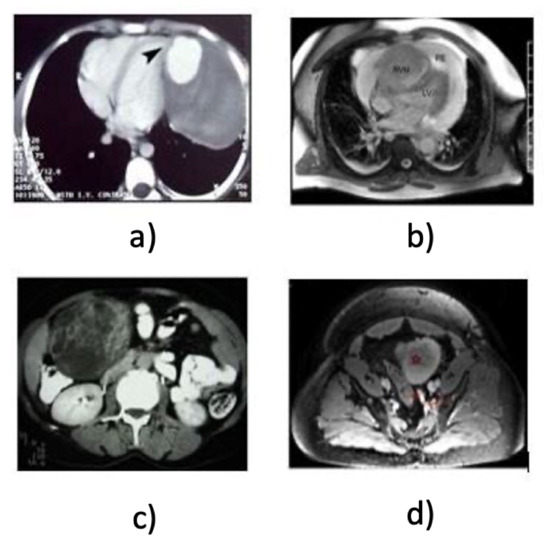

- We discuss the problem of intra-class and inter-class variability in medical image classification.